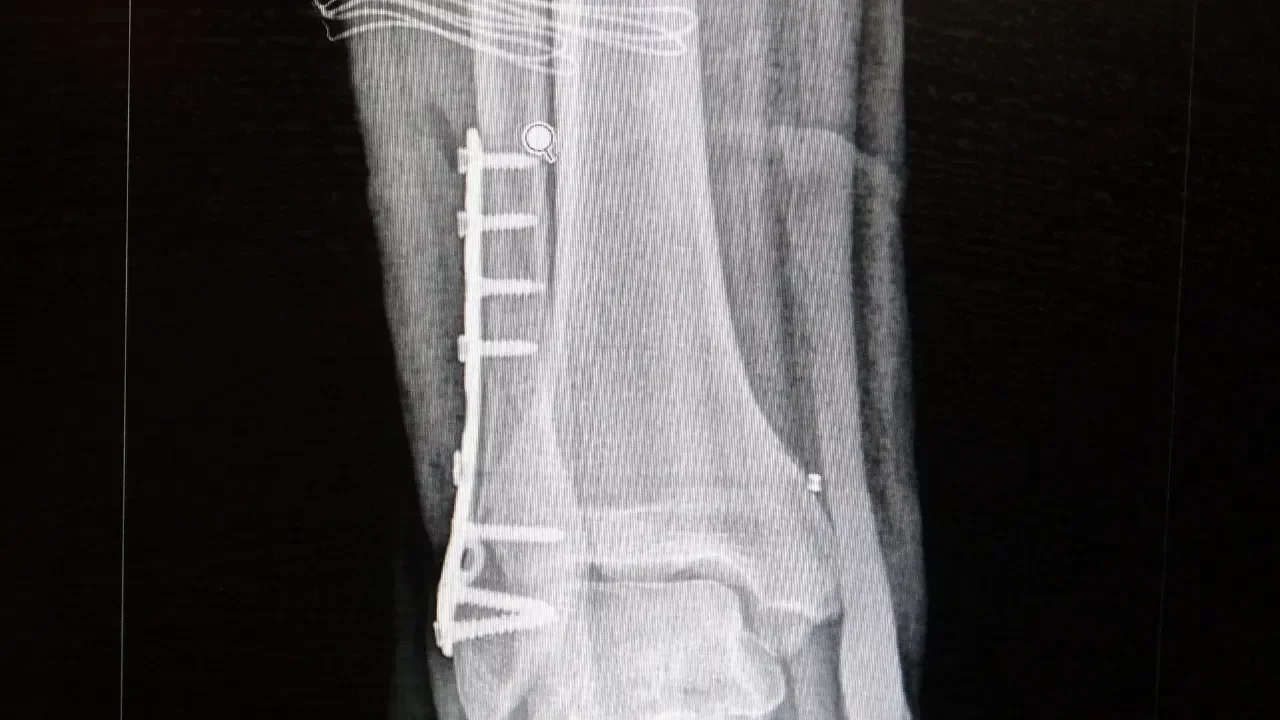

Ortopedi polikliniklerine en sık ayak bileği, diz ve omuz yaralanmalarıyla başvurulduğunu belirten Demirbaş, futbol nedeniyle yaralanma oranlarının da ilk sırada yer aldığını söyledi. Konuya ilişkin Demirbaş, "Futbolda menisküs yırtıkları, ön çapraz bağ yırtıkları, iç ve dış yan bağ yaralanmaları, aşil tendon kopmaları ve ayak bileği bağ yaralanmaları çok sık görülüyor. Ayrıca spora bağlı kırıklar da önemli bir yer tutuyor" ifadelerini kullandı.